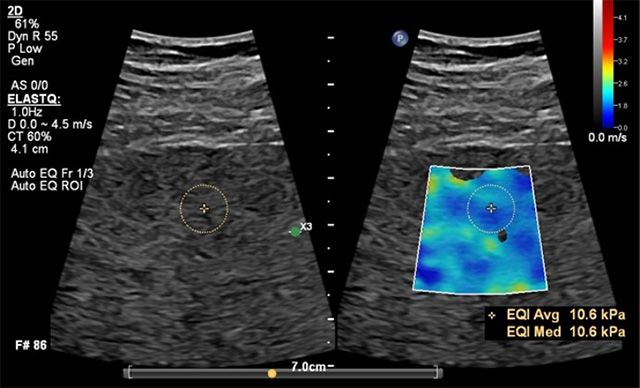

필립스코리아는 AI 기반 자동화 솔루션을 탑재해 심장 진단의 정밀도를 높인 ‘어피니티(Affiniti) VM 11.0’, 간 섬유화 검사 기능인 ‘오토 엘라스트큐(Auto ElastQ)’를 추가한 ‘에픽 엘리트(EPIQ Elite - VM 12.0)’ 등 다양한 임상 분과에서 활용할 수 있는 최신 초음파 포트폴리오를 전시한다. 특히 에픽 엘리트는 AI 기반 자동 프레임 분석과 자동 설정 기능을 통해 검사 시간을 60% 단축하고 조작 횟수를 29% 줄여 의료진의 업무 효율을 높이는 것이 특징이다.